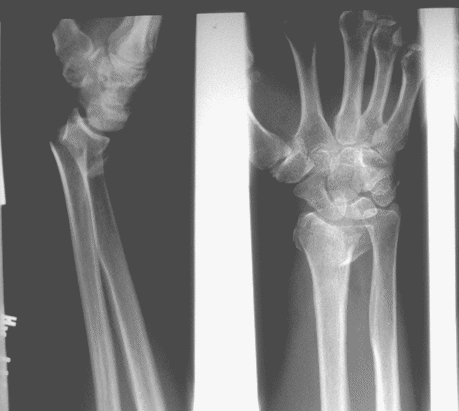

Case 3 Preop

Case3 Preop